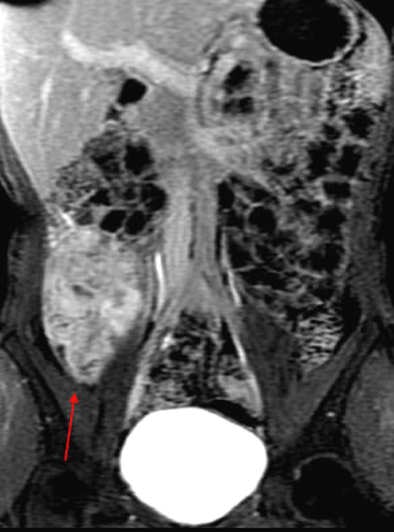

MRI results were then compared to colonoscopy and pathology reports to determine the presence or absence of disease in evaluable bowel segments. Individual imaging parameters (including wall thickening, enhancement, T2 signal, mesenteric vascular prominence, and adenopathy) were also separately analyzed to determine their independent predictive value, the authors wrote.

The study team acquired steady-state free-precession (SSFP) images of the abdomen and pelvis (TR= 4 ms, TE = 2 ms, slice thickness 8 mm for coronal images and 8-mm for axial images). Axial and coronal fat-suppressed half-fourier single-shot fast-spin echo (SSFSE) and axial spoiled-gradient images were also obtained through the abdomen, followed by T1-weighted fat-suppressed spoiled-gradient echo (LAVA/VIBE) images, before the injection of 1 mmol/kg of gadopentate dimeglumine contrast (Bayer Healthcare) followed by a saline flush and postcontrast imaging.

A single experienced abdominal radiologist, blinded to the final results, interpreted all of the MRE images, rating wall thickness, abnormal enhancement, abnormal T2 signal, and mesenteric vascular prominence on a scale of 1-4. All endoscopy reports were reviewed for mention of inflammatory changes in specific bowel segments, and pathology reports were reviewed for the presence of inflammatory disease, the study team reported.

Interestingly, the results were in line with smaller studies that used antiperistaltic agents, they wrote. As in those studies, MRE showed its real strength in a couple of features of active Crohn's disease. "Analysis of individual MR parameters demonstrates that wall thickening and abnormal enhancement are the most sensitive indicators of Crohn's disease on MRE while abnormal T2 signal, mesenteric vascular engorgement, and adenopathy were insensitive but specific," he wrote.